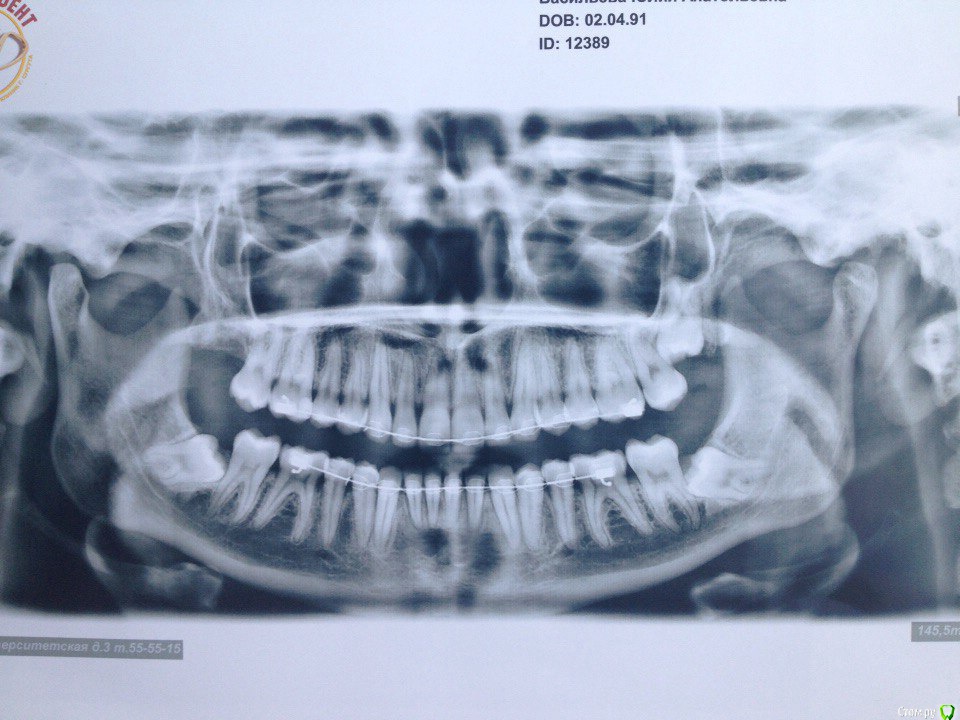

Поставила керамические брекеты в марте 2015 года, ставила для выравнивания зубов (торчали два передних зуба на нижней и на верхней челюсти), проблем с ВНЧС не было, только скрипела во сне зубами, муж неоднократно замечал. На первичной консультации отртодонта предупредила о бруксизме, сказал все нормально, все подобные проблемы именно брекетами и лечатся. Перед установкой делали только ОПТГ и фотографии. Прикус был немного глубокий, как я сама понимаю, во всяком случае от врачей никогда не слышала, что у меня какой-то неправильный прикус. Через месяц после ношения брекетов перестал открываться рот, просто к вечеру я заметила, что не могу его открыть широко, не влазила даже ложка, на осмотре у ортодонта он немножко подпилил накладки, которые были установлены на 6 зубах на НЧ. Ничего не изменилось, на след.осмотре убрал накладки совсем, рот начал открываться, через щелчок или хруст, но не прямо, для широко открытого рта мне приходится делать движение вправо и только так рот открывается до конца, сильных болей не было и нет, бывает ноет в левой стороне возле уха. через несколько месяцев ношения брекетов начала замечать, что челюсть уходит вправо. Вообще на протяжении всего ношения брекетов испытывала дискомфорт в мышцах, все тянуло, и какие то тяжелые челюсти казались. 15 мая сняли брекеты, сделали слепки для капп, мой ортодонт сказал, что сейчас нужно удалять все оставшиеся 8 и походить к остеопату или мануальщику, если не поможет возвращаться делать аксиографию и ставить другие брекеты, на вопрос чем они отличаются он ответил, что с ними можно зуб наклонять в любом положении, в отличии от этих, т.к. с этими брекетами зубы встают только на 90градусов, после снятия брекетов чувствую себя хуже, боль начала появляться в левом ухе, ужасно все напряжено. В нашем городе гнатологов и подобных специалистов нет, ходила на протяжении года к нескольким ортодонтам на консультацию никакой конкретики, грубо говоря все пожимали плечами, не знаю как быть, какие обследования пройти, не поторопились ли мы снимать брекеты (он настаивал), и к кому обратиться, ваше мнение с чем это связано и как теперь решить проблему?